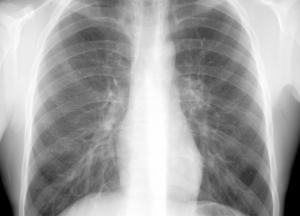

Заболевания легких представляют собой довольно серьезную и распространенную во всем мире проблему, основными методами предотвращения которой является отказ от курения, занятия упражнениями, избежание загрязнений воздуха и употребления полезных продуктов, - передает FaceNews.ua.